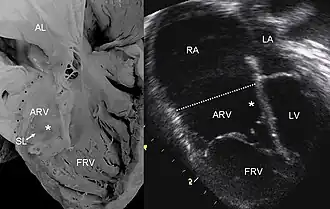

Pathologische hartdoorsnede vergeleken met een echo bij de ziekte van Ebstein. | ||||